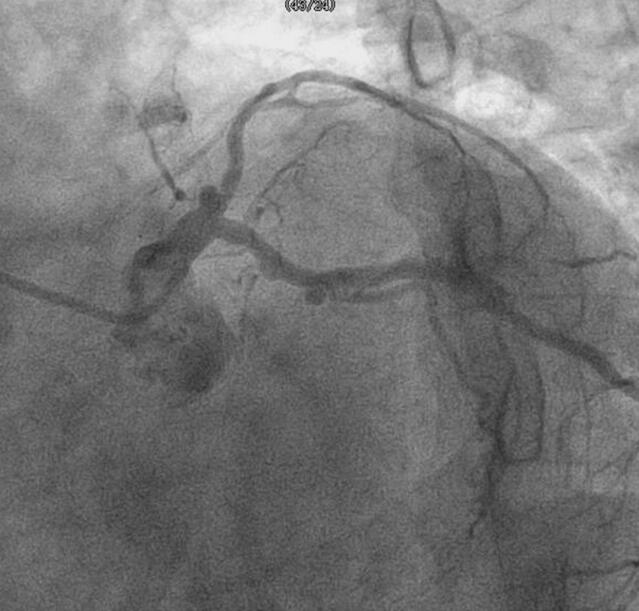

出院后长期标准西医药物+中医汤药治疗。西药如上,间断口服呋塞米片20mg,每日1次或隔日1次。患者在我院就诊期间及出院之后长期定期随诊,除了规范应用西药外,一直服用汤药。憋气、畏寒、乏力及水肿症状渐消失,日常活动恢复正常,仍体质较弱。舌淡暗红,苔少薄白,脉弦细。出院后,患者中药以后按四逆汤、参麦散、参苓白术散、六味地黄汤加减。1年后停用生脉散。具体根据证候变化,调整方剂剂型及剂量,包括温阳的淫羊藿、仙茅、桂枝、吴茱萸、山萸肉等;理气药物枳实、厚朴等;其中制附片渐增加到50g。患者2008年11月,2010年5月第二次住我院检查。2008年11月心脏超声:①左心增大,左室舒张末径67mm,右心房室内径正常;②各瓣膜形态结构未见异常,收缩期二尖瓣房侧见少量反流信号;③室间隔变薄,室壁运动弥漫性减低;④舒张期二尖瓣口前向血流A 峰55cm/s,E 峰29cm/s,EF:34%。心脏门控血池断层显像:左室腔明显增大,心尖部反向搏动,各室壁运动幅度明显降低,协调性差,LVEF:10%,RVEF:54%。BNP:1272pg/ml。2010年5月心脏超声:①左心增大,左室舒张末径78 mm,右心房室内径正常;②各瓣膜形态结构未见异常,收缩期二尖瓣房侧见少量反流信号;③室间隔变薄,运动明显减弱,余各节段室壁运动未见异常;④升主动脉及其根部不宽,搏动减弱,主肺动脉不宽;⑤舒张期二尖瓣口前向血流A 峰73c m/s,E 峰48c m/s,L VEF:40%。BNP:523pg/ml。复查冠脉造影(图090‐1、图090‐2):冠状动脉供血呈右冠优势型,左、右冠状动脉走行区可见钙化,左主干未见异常,前降支近段原支架100%闭塞,对角支较大,血流通畅,TI MI 血流3 级;回旋支支架内未见狭窄,远段90%×10mm 狭窄,钝缘支近段90%×10mm 狭窄;右冠状动脉中段70%×20mm 狭窄,锐缘支开口80%狭窄,前向血流TI MI 3 级。冠状动脉造影结论:冠状动脉粥样硬化性心脏病,三支病变,累及前降支、回旋支、右冠状动脉,前降支支架内再狭窄(100%闭塞)。

图090‐1 右冠脉造影

图090‐2 前降支近段支架内100%再狭窄